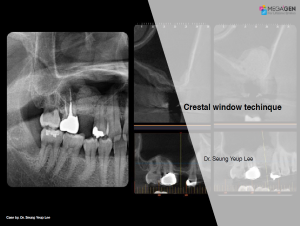

Keywords

e.g. product name, treatment solution, author, clinician name